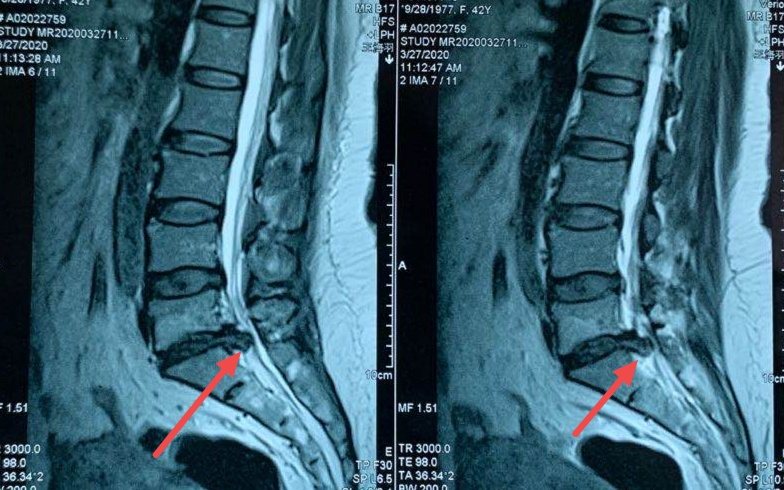

6)影像学指标佐证以上者。